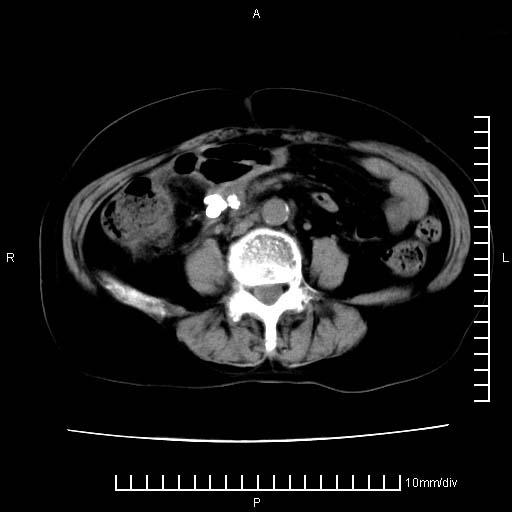

下腹疼痛2月,加重并呕吐2天,下腹压痛,反跳痛。白细胞1万2.

下腹至盆腔较大包块,与邻近肠管关系密切,下腹疼痛2月,加重并呕吐2天,下腹压痛,反跳痛。白细胞1万2.

由于没有做肠道准备很难分清是哪根肠管,但看位置考虑为升结肠回盲部的问题,我首先考虑化脓性阑尾炎,不除外结肠癌合并感染化脓。建议做增强进一步明确。

补充:道格拉斯腔内有积液,且密度较高,显然提示有感染。

考虑右侧卵巢囊肿伴感染可能性大。

附件实性肿块有坏死 考虑卵巢癌

来源于附件占位—多考虑:卵巢癌!

不知道大家可要注意下腹腔小肠旁不规则结节状灶,部分钙化,是否要考虑小肠腺癌.盆腔包块可能考虑脓肿.